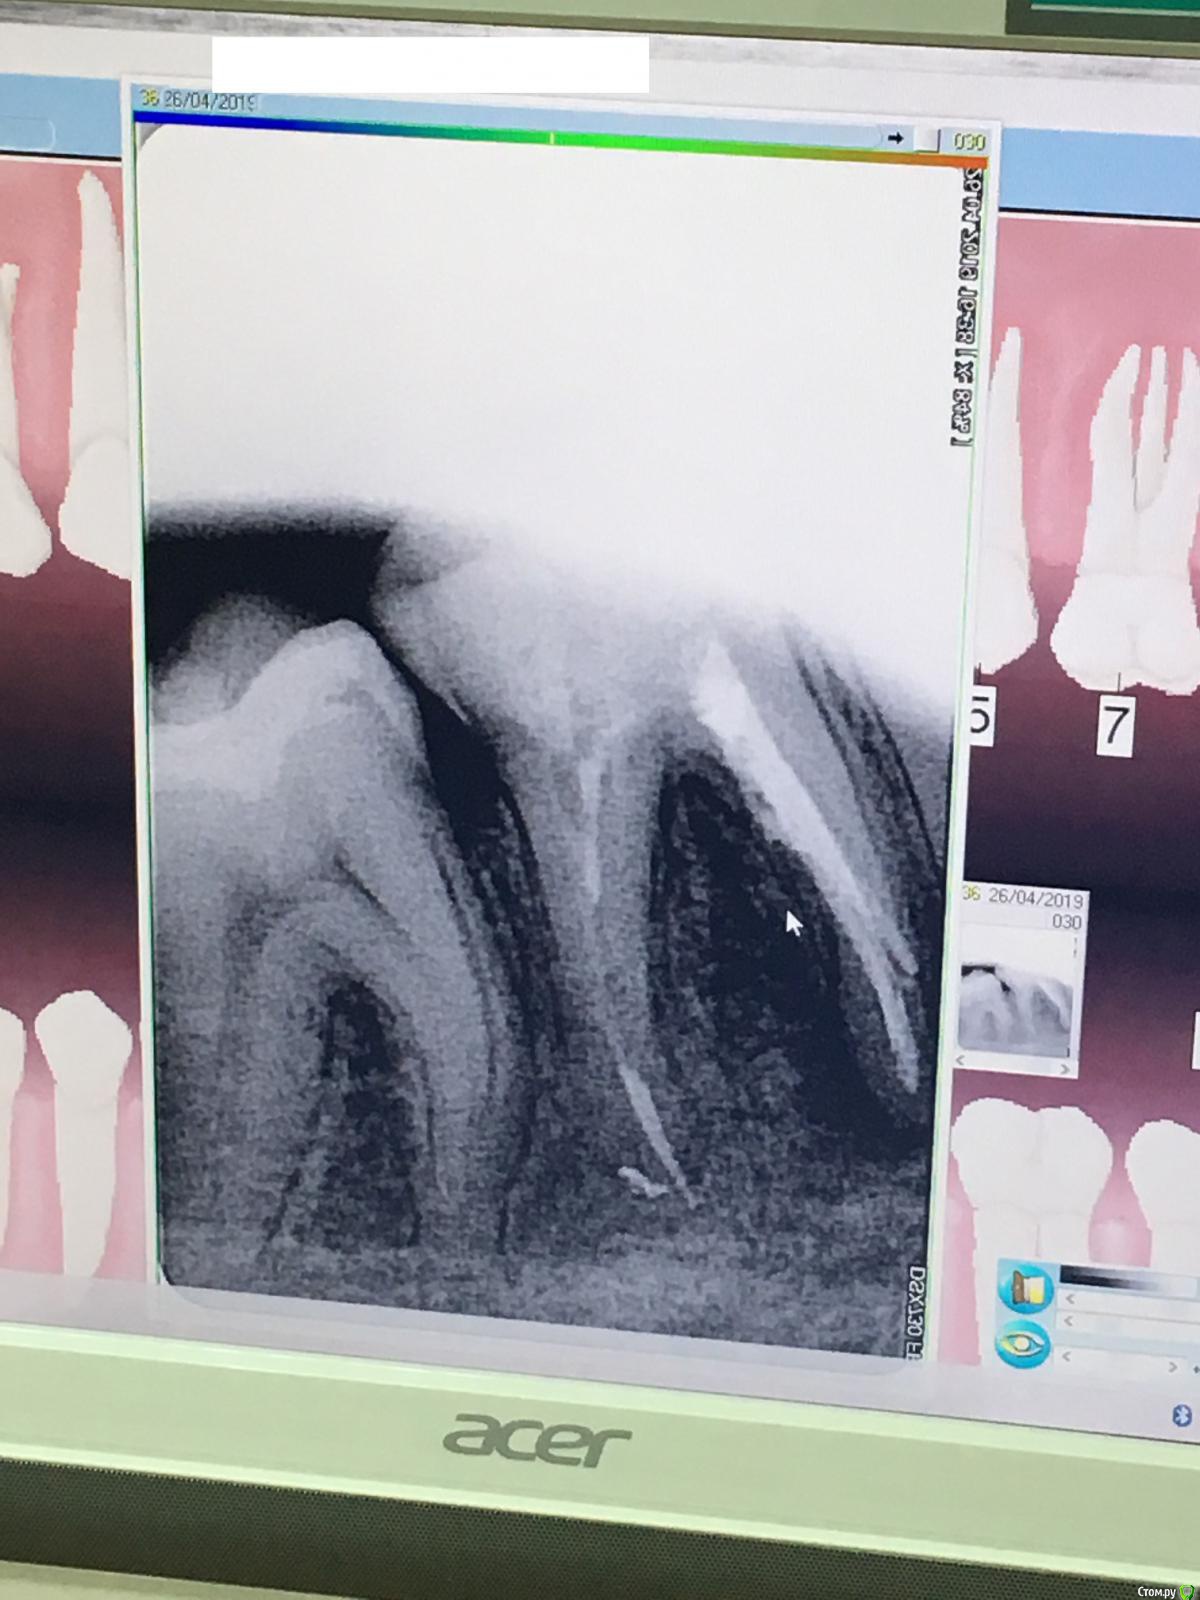

nashe72 Опубликовано 27 апреля, 2019 Автор Поделиться Опубликовано 27 апреля, 2019 Всем привет.Сделал снимок спустя пол года. Зуб особо не беспокоит, но периодически слегка ноет и опухоль со стороны щеки осталась. Пальцем не прощупывается, языком чувствуется отчетливо.Хотел бы спросить ваше мнение по поводу снимка, стало ли хуже, чем на предыдущих фото? И еще не могу понять, куда делся материал из левого канала? Врач, делающий снимок, не смог дать ответ. На снимке в ноябре, сразу после лечения, канал заполнен, на этом, он полупустой. Это чем то может грозить мне? Ссылка на комментарий